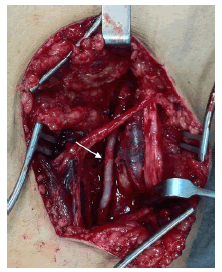

Con la confirmación diagnóstica de enfermedad quística de la adventicia, se decidió intervenirlo quirúrgicamente. Se utilizó un abordaje posterior de la fosa poplítea (figura 4) que expuso la lesión quística dependiente de la pared arterial. Se resecó el segmento afectado (figura 5) y se reparó el defecto con intercalación de injerto autólogo de vena safena (figura 6). El paciente evolucionó favorablemente, sin complicaciones inmediatas. Acudió a control meses después de la cirugía, sin síntomas. Se practicó una angiografía por tomografía computadorizada (TC) de control, que demostró un adecuado flujo sanguíneo en el injerto (figura 7).